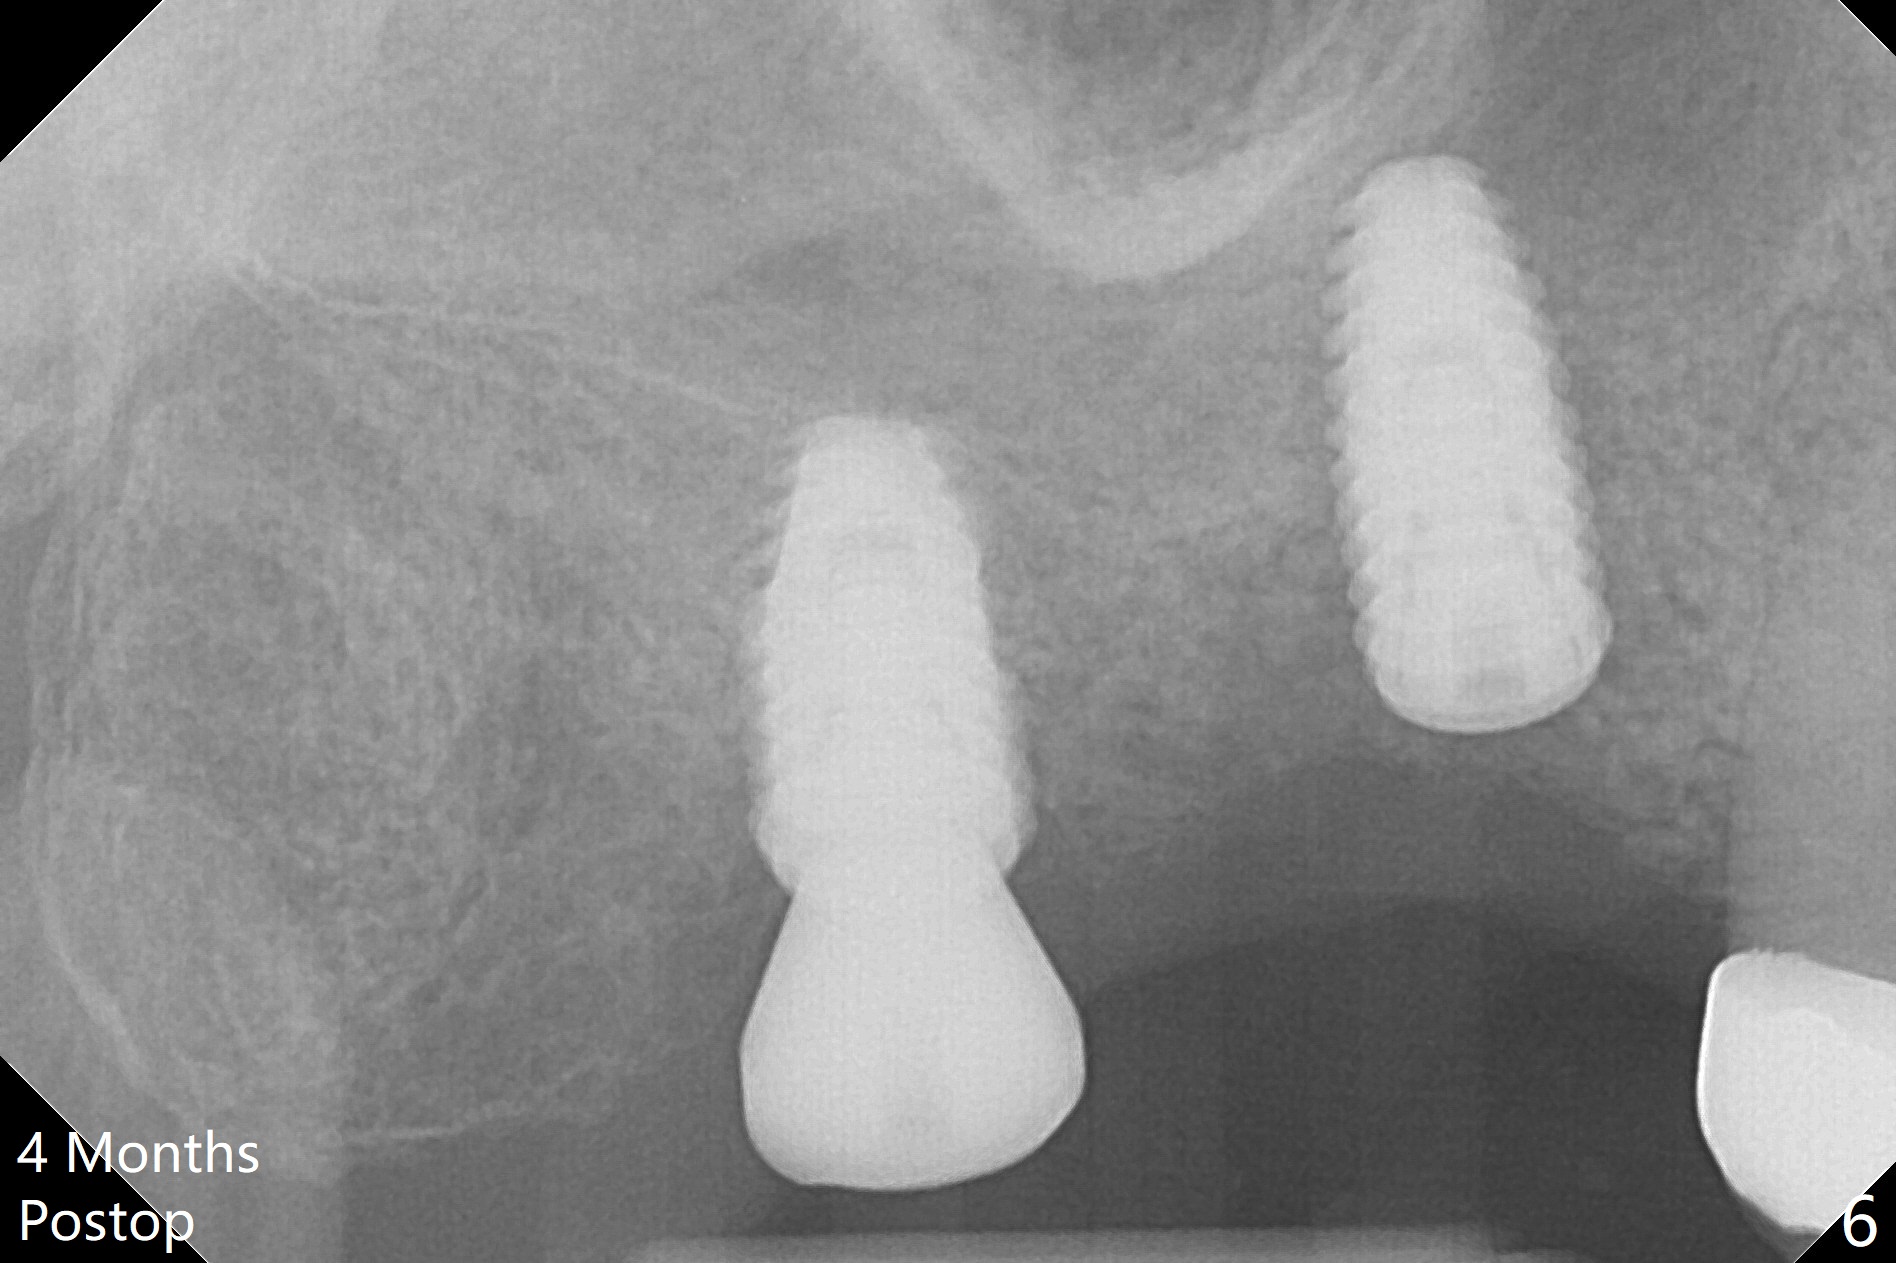

Osteotomy at the sites of #2 and 3 goes on as planned. Sinus lift using DIO 2.8 mm round bur with 6 and 7 mm stoppers (respectively) is carried on without certainty, because it is difficult to feel the stop through the osteotomy. The crest may be uneven or soft. It appears that the soft tissue landmark as a stop may be easier to identify. In fact a 3 mm IBS Magic Expander (an osteotome) was used for sinus lift at #3. The 2 implants are placed with 20 and 30 Ncm (Fig.1,2). Healing abutments are inserted. At 2-week follow-up, the patient reports "pain a few days earlier, took a pill of antibiotic, pain gone. UR metal is sharp". She does not take antibiotic regularly. Exam reveals that there is heavy plaque around #2,3 healing abutments. The buccal edge of #2 abutment is trimmed for comfort. Nearly 1 month postop, #3 healing abutment dislodges with buccal gingival erythema and edema with purulent discharge (Fig.3). Healing screw is placed at #3 with Amoxicillin and Chlorhexidine prescribed. One week later, the implant at #3 turns when the healing screw is retightened (Fig.4). After debridement, Vanilla graft is placed. There is no infection at #2 or 3 four months postop (Fig.5,6); the lingual gingiva is erythematous and edematous at #29 with mobility II (Fig.7 (vertical root fracture)). Uncover is conducted at the site of #3; there is no infection superficial 7.5 months postop (Fig.8). There is a large buccal defect upon incision with dark hemorrhage. In fact the bone density is low crestally (Fig.8 *). Bone graft is placed for the 2nd time. Eleven months later (1.5 years post implant placement), the bone regrows crestal (Fig.9 *). The crown at #3 is loose 1 year 5 months post cementation (Fig.10). After proximal trimming (Fig.11 *), the abutment at #3 is seated completely. After lab repair, crown oral cement, crown/abutment removal for excess cement removal, the crown/abutment cannot be torqued >25 Ncm (Fig.12, 30 Ncm). PA shows incomplete seating (Fig.12 <). Then the crown is sectioned so that the abutment has more freedom to be seated completely with pressure against the gingiva (the patient feels pain, Fig.13). Torque is 30 Ncm. After crown cementation, the abutment will not be removed for cement removal.